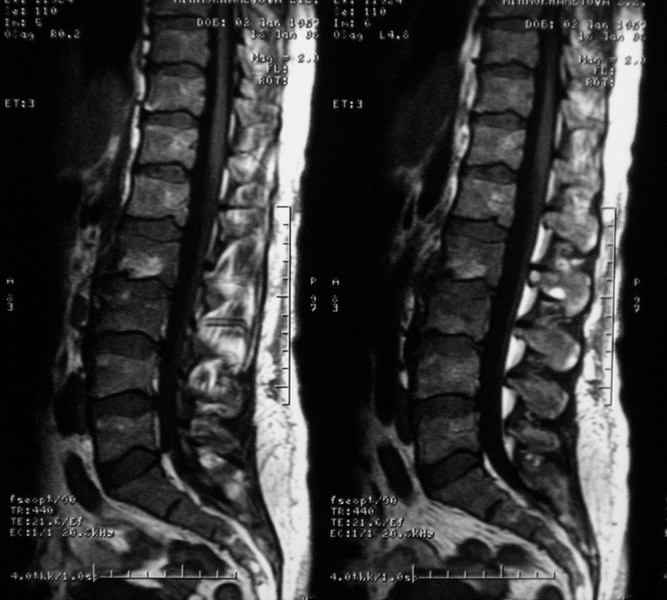

Отправляю MRI в динамике, снятые с пленки на фотоаппарат.